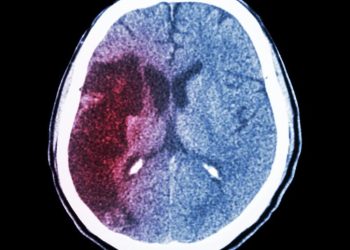

Read moreA hemorrhagic stroke is a medical emergency caused by a ruptured blood vessel in the brain. It cuts off oxygen...